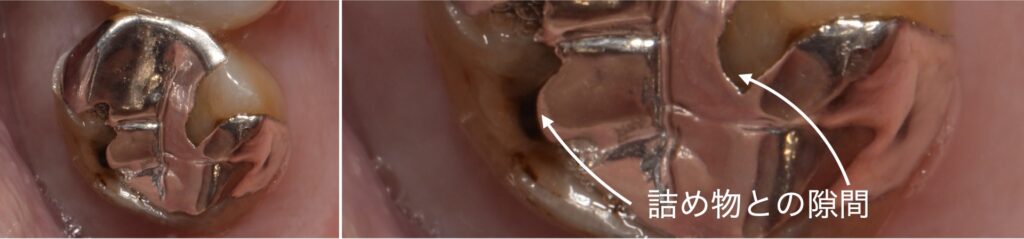

2:隙間があいている詰め物

~徹底的な精密治療~

上記左側の写真のように、一見封鎖性のよい詰め物に見えたとしても、右側写真のように歯科用顕微鏡(マイクロスコープ)を用いた拡大写真を見ると、隙間にプラークが入り込んでいることがわかるかと思います。

細菌の大きさは約1ミクロンから3ミクロンと言われており、これは1000分の1ミリから1000分の3ミリです。

細菌が侵入できないような精度の高い詰め物を作製することは並大抵なことではないとわかると思います。